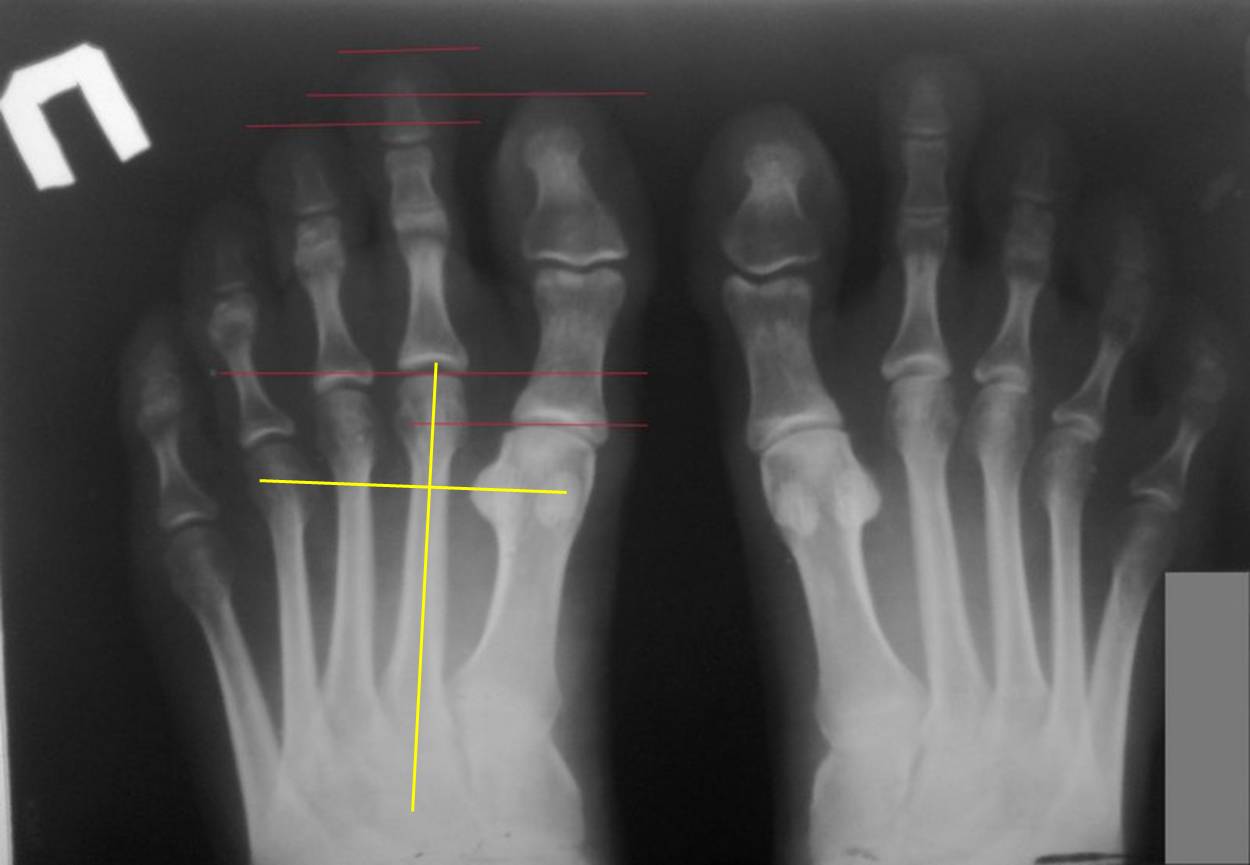

Хорошо, что пациентка отказалась от удлинения 1 плюсневой. Это привело бы к быстрому развитию hallux limitus и артроза.

А почему Вы подумали, что 1 плюсневые укорочены? На представленной Вами рентгенограмме я провел перпендикуляр к оси 2 плюсневой кости на уровне середины латеральной сесамовидной. Линия прошла точно через середину головки 4 плюсневой. Это норма. То есть, длины 4 и 5 плюсневых соответствуют длине первой. А вот длины 2 и 3 плюсневых значимо преобладают над длиной первой. В такой ситуации развитие молоткообразной деформации 2 пальца вполне естественно. Есть ли у пациентки натоптыш под головкой 2 плюсневой? Пусть даже и бессимптомный. Если есть, то лучше всего совместить укорочение основной фаланги с остеотомией 2 плюсневой по Вейль. Сама по себе эта остеотомия дает укорочение до 3-5мм. И одновременно позволяет вывести из-под повышенной нагрузки головку 2 плюсневой. Вмешательство на фаланге и плюсневой кости можно делать из одного доступа.